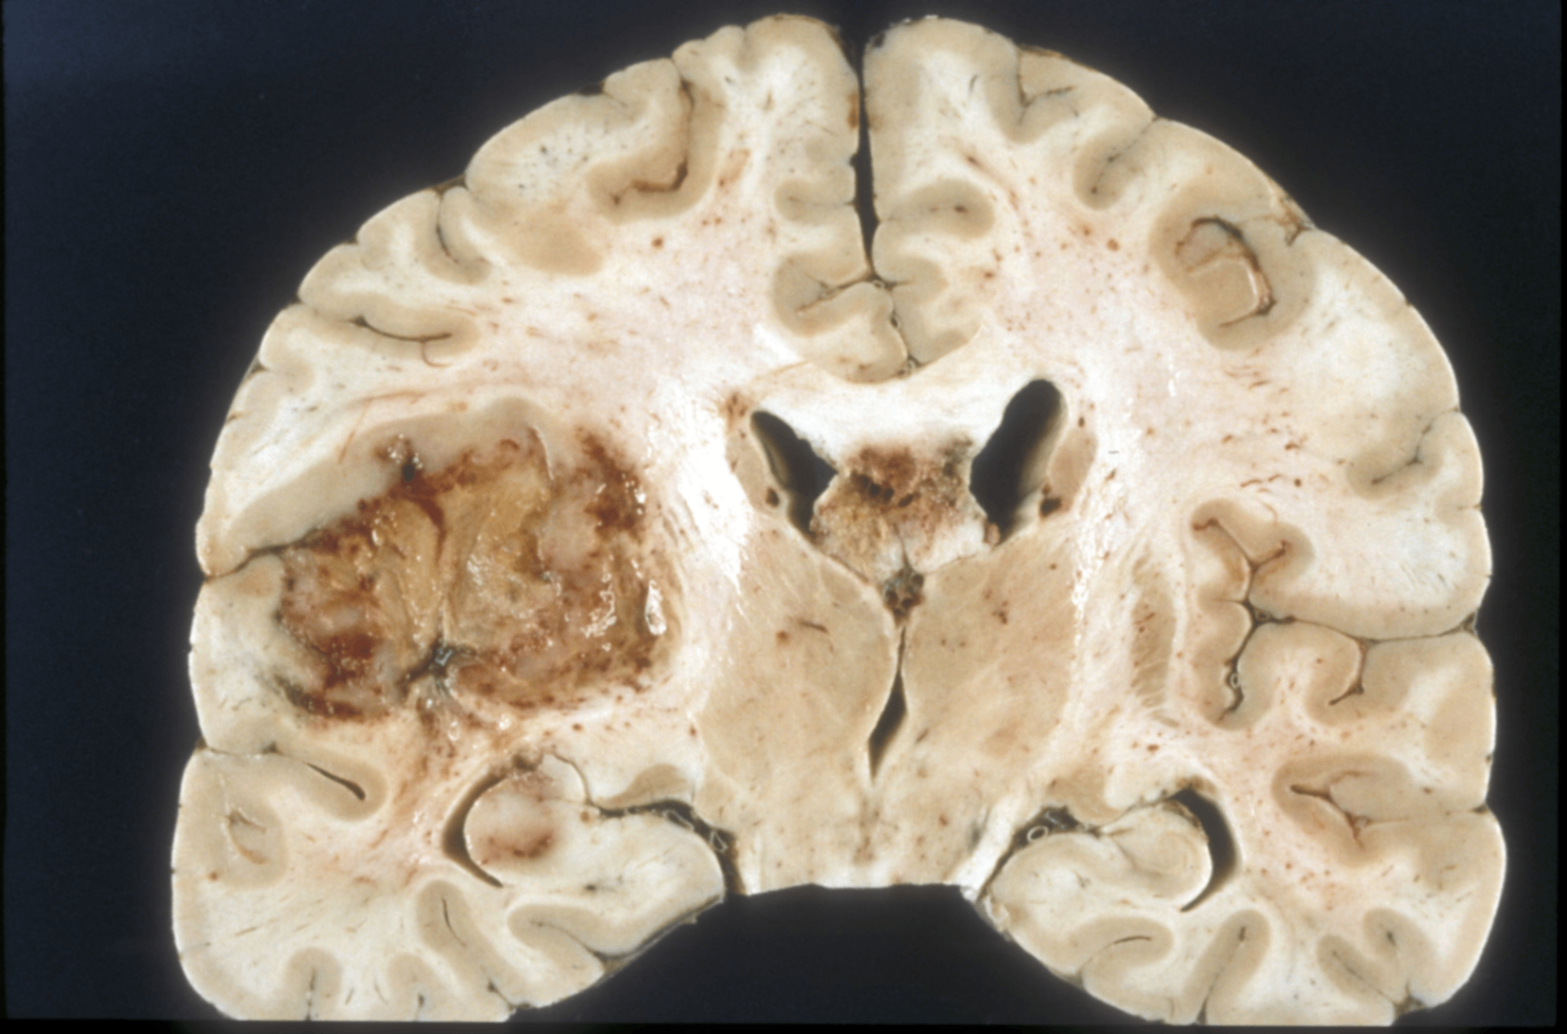

1. 교모세포종 (Glioblastoma)

성상세포에서 기원한 악성 뇌종양(WHO grade IV)으로, 성인에서 가장 흔하고 예후가 매우 불량한 신경교종

2) 병리소견

• 종양 세포는 과세포성(hypercellularity)을 띠며, 길게 늘어진 또는 불규칙한 과염색 핵을 가지며, 섬유질 배경(fibrillary background) 속에 위치

배경은 GFAP(교세포 섬유산성 단백질) 양성

Serpentine pattern의 괴사와 미세혈관 증식(microvascular proliferation)이 특징적

- 괴사 주변에 종양세포가 방사형으로 배열된 palisading necrosis 관찰됨

- 저산소증(hypoxia)에 반응하여 악성 성상세포가 VEGF를 분비 → 미세혈관 증식 유도